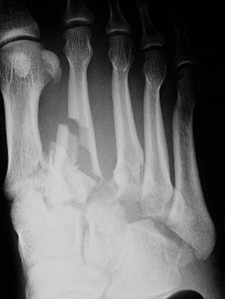

Question 28:

A 58-year-old male with poorly controlled type 2 diabetes presents with a unilaterally swollen, red, and warm right foot. There are no open ulcers. Radiographs show severe fragmentation of the tarsometatarsal joints, periarticular debris, and joint subluxation. ESR and CRP are within normal limits. Based on the Eichenholtz classification, what stage is this patient in, and what is the standard initial treatment?

Options:

- Stage 0; Custom diabetic footwear

- Stage 1; Total contact casting

- Stage 2; Midfoot arthrodesis

- Stage 3; Charcot Restraint Orthotic Walker (CROW)

- Stage 1; Intravenous antibiotics and ID

Correct Answer: Stage 1; Total contact casting

Explanation:

The clinical and radiographic presentation is classic for acute Charcot neuroarthropathy. The normal inflammatory markers help distinguish this from acute osteomyelitis. Eichenholtz Stage 1 (Developmental/Fragmentation) is characterized by erythema, swelling, warmth, and radiographs showing osteopenia, fragmentation, joint subluxation, and debris. The gold standard treatment for Stage 1 Charcot is strict immobilization and offloading, typically using a total contact cast (TCC) until the erythema, warmth, and swelling resolve, and radiographs show consolidation (Stage 2/3).